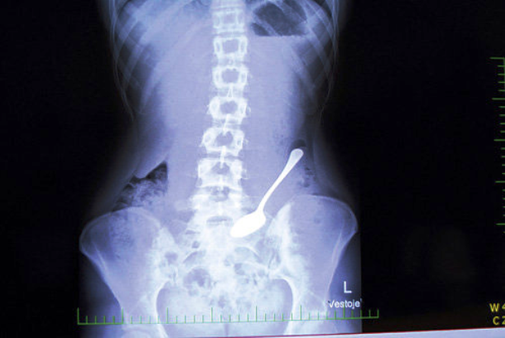

ચમચી

એક 33 વર્ષીય મહિલા ભૂલથી ચમચી ગળી ગઇ. તેના મોઢામાં માછલીનો કાંટો ફસાયો હતો અને તેને નીકાળવા માટે તેને જ્યારે ચમચીનો ઉપયોગ કર્યો તો તે પણ ગળાઇ ગઇ. આને કહેવાય બાવાના બેય બગડ્યા